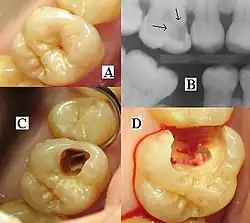

Entwicklung der Karies mit Darstellung der Symptomatik

A) Sondierbare Karies

B) Röntgenologische Diagnostik

C) Eröffnung der Kavität

D) Caries profunda mit Eröffnung der Pulpa